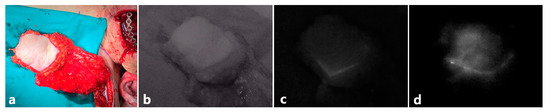

3.1. Clinical Evaluation